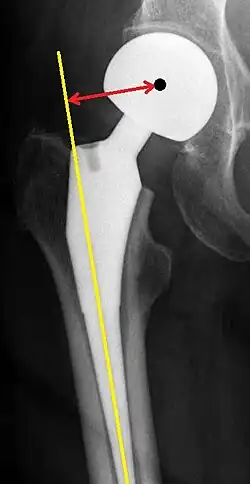

Femoral (neck) offset is defined as the perpendicular distance between the intramedullary or longitudinal axis of the femur and the center of rotation of the native or prosthetic femoral head. An offset of less than 33 mm is associated with hip dislocation.[99][100]